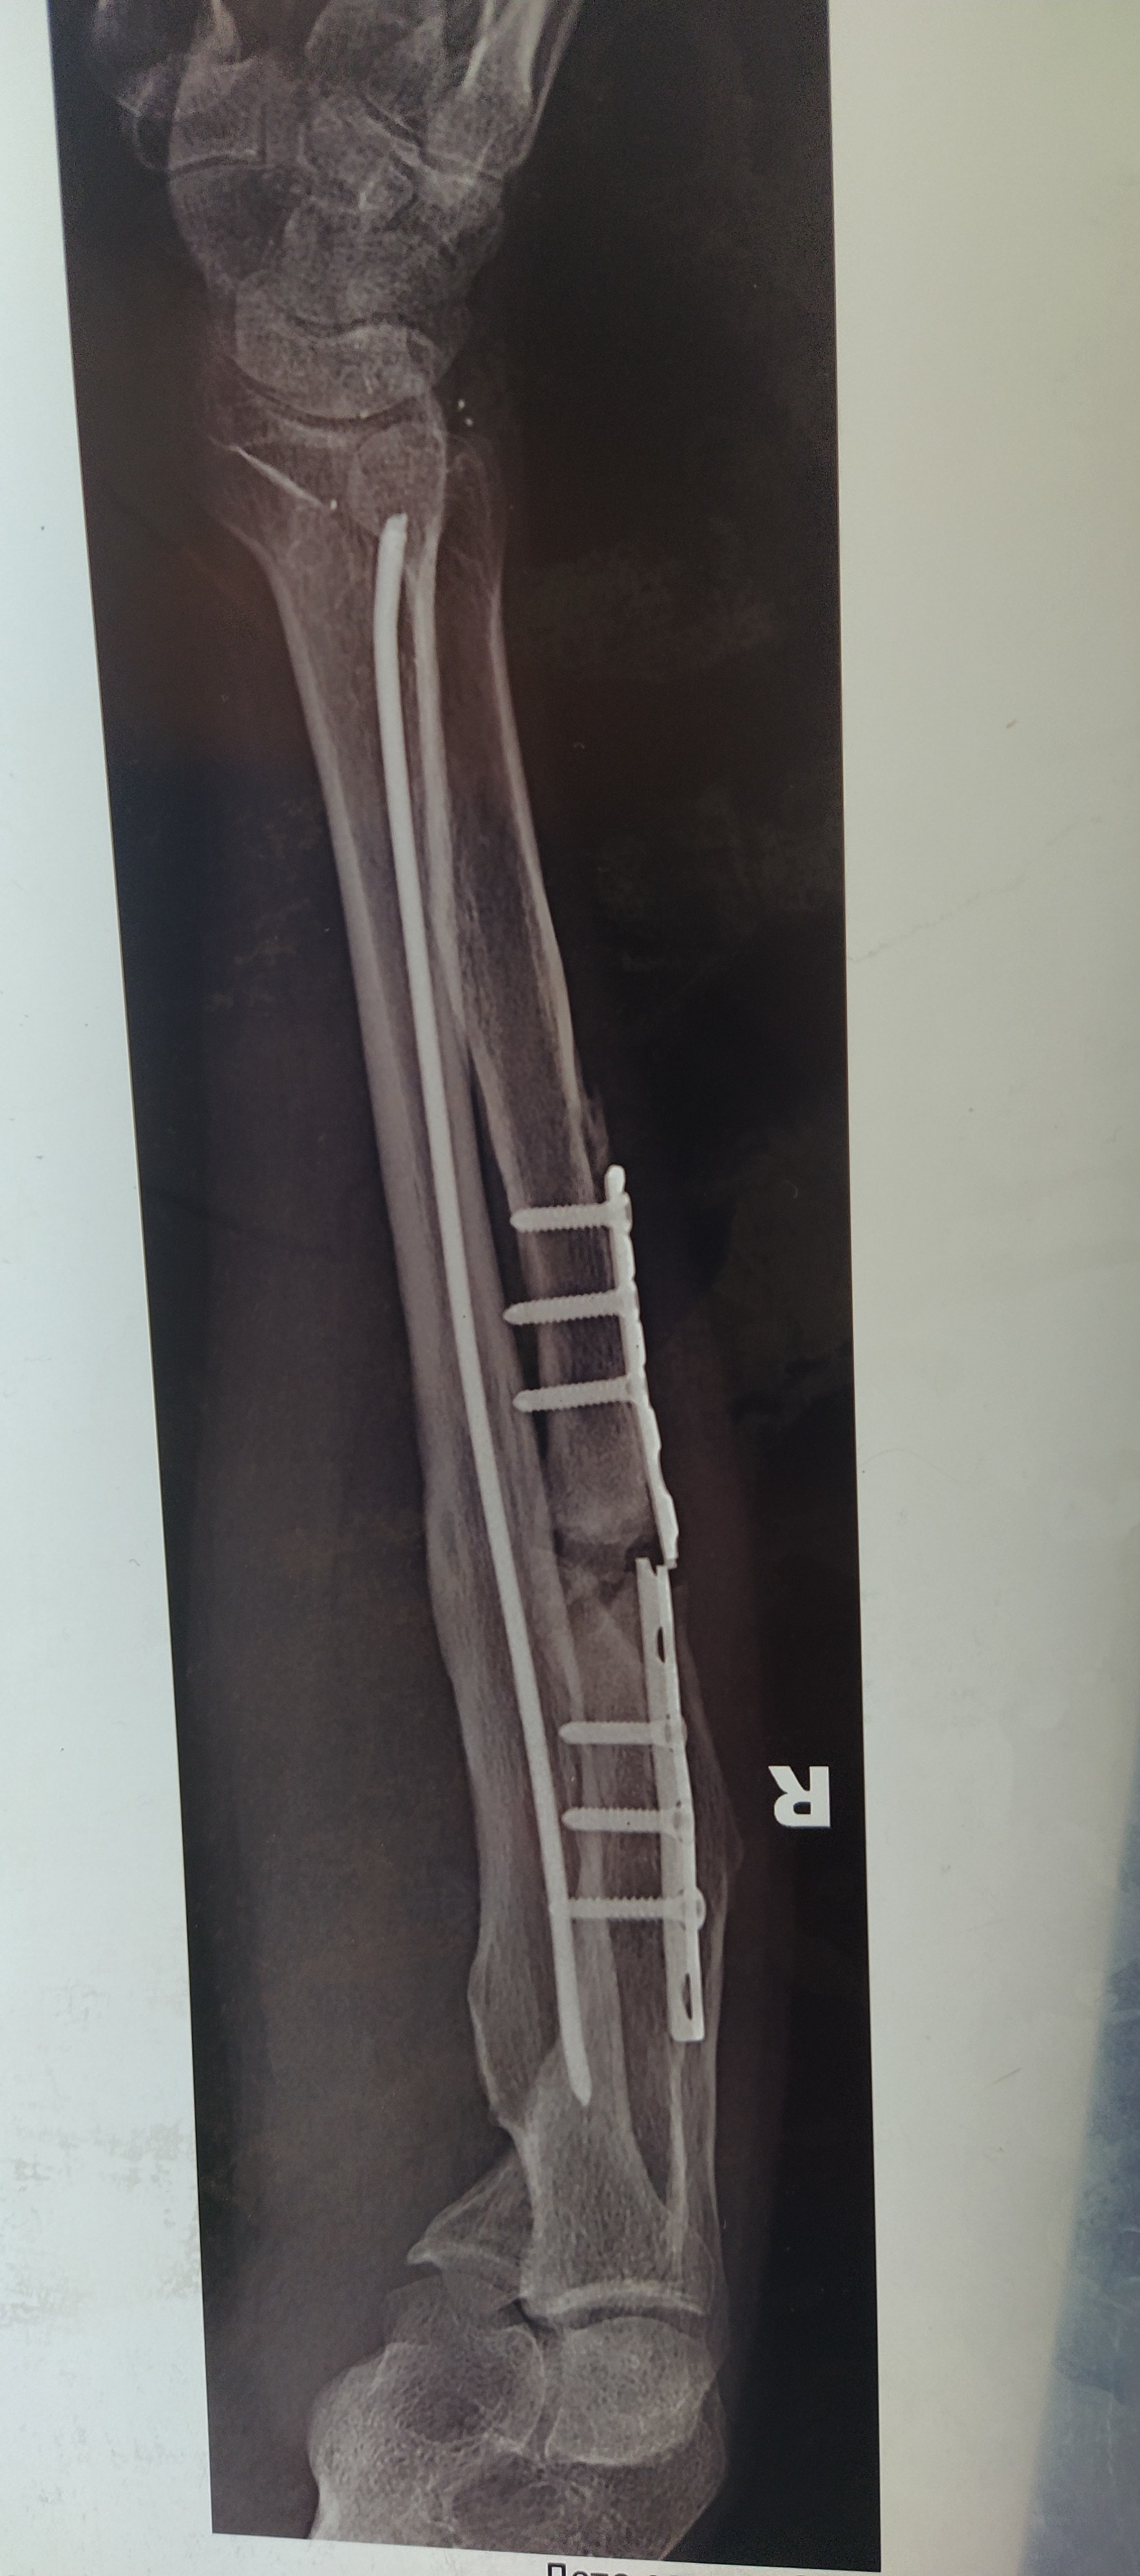

Их задача была вытащить штырь и поставить новую титановую пластину.

После операции подошёл мой лечащий врач и сказал , что спицу они не смогли вытащить и она осталось навсегда. Ну как можно конечно, но это заново ломать кость☹️

После приезда домой наблюдался 3 месяца в местной поликлиники у хирурга и меня выписали. Пошел на работу, но летом заболела рука и почувствовал что опять хрустит рука,ну всё сломалась пластина подумал! И вот итог пластина сломана рука не срослась.

А это уже 7@я операция на руку была и врач сказал "Чем больше мы туда вмешиваемся тем хуже для тебя"